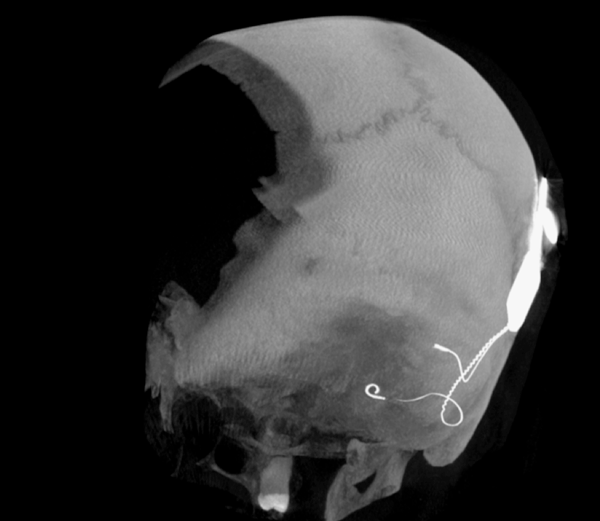

Both patients were imaged immediately with CBCT using SCANORA® 3Dx (Soredex, Tuusula, Finland). The field of view (FOV) was 140 x 165 mm and voxel size 0.2 mm. Imaging parameters were 90 kV, 8 mA, 4.00s. Standard 1 mm axial, coronal and sagittal reformations were made, as well as MIP and 3D reconstructions using OnDemand3D™ software (Cybermed, Seoul, South Korea).

CBCT proved to be optimal for imaging of these implants because of the superior bony delineation and nearly artefact free images. All four parts, i.e. the receiver stimulation part, extracochlear electrode implanted on the surface of the temporal bone, the extracochlear electrode plate and the intracochlear electrode array could be well imaged with CBCT.

On CBCT all four of the important parts of the implant were very well seen both on the axial slices and three dimensional surface reconstruction images. The implant is placed on magnetic plates, and the extracochlear part was seen in an abnormal separated position. The intracochlear electrode array showed no signs of separation in either of the cases. The intracochlear electrodes were well seen in both of the cases.

The optimal images of these two patients are shown in the radiographic illustrations in Figures 1-7.

Figure 4: 3D MIP image of patient 2.